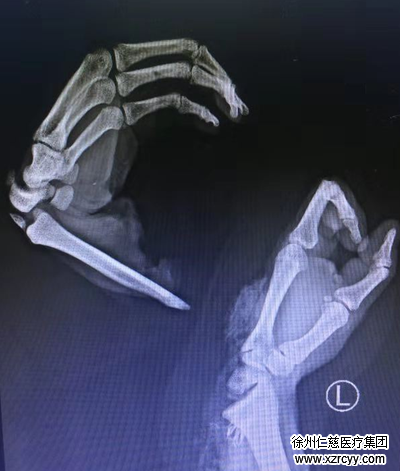

术中探查发现,患者左前臂尺侧中段至左手第3掌指关节斜行完全离断,左尺骨骨折,左桡骨远端关节面骨折,舟状骨、大多角骨等多处骨折,腕关节脱位,韧带破裂,多处血管断裂……